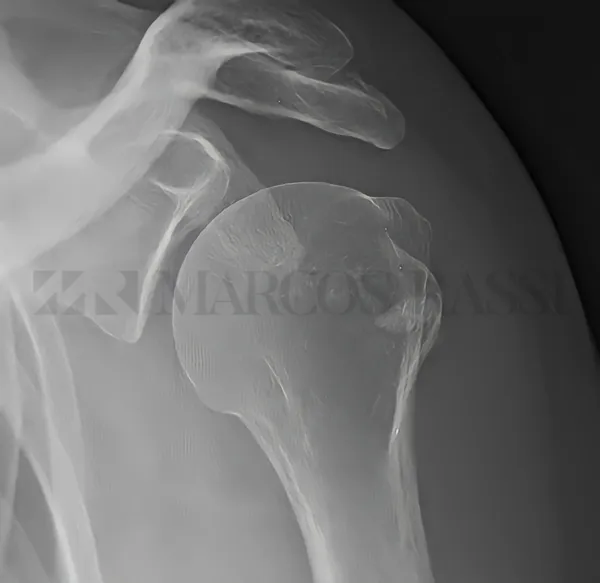

A lesão do manguito rotador é uma doença comum que se caracteriza por ruptura de um ou mais tendões do ombro. Afeta pessoas ativas de meia idade, sendo mais frequente nas mulheres. A progressão da lesão é o principal problema e o procedimento artroscópico visa a cicatrização do tendão no osso (local de origem), de forma menos invasiva. Utiliza-se âncoras bioabsorvíveis e fios de sutura para o devido reparo tendinoso.

A instabilidade anterior do ombro é uma doença comum que se caracteriza por várias recidivas (deslocamentos), em virtude de ter ocorrido uma ruptura do lábio anterior associada ou não à perda óssea da glenoide e/ou cabeça umeral, após o primeiro episódio. O trauma é o principal agente causador. Afeta pessoas jovens, às vezes abaixo dos 20 anos de idade. O procedimento artroscópico visa a cicatrização do lábio anterior com retensionamento da cápsula articular, por meio de miniâncoras e fios de sutura.

A tendinite calcária é uma doença comum que se caracteriza por depósitos calcários no interior de um ou mais tendões que compõem o chamado manguito rotador. O supraespinhal é o mais acometido. O motivo do seu aparecimento é incerto. Afeta mais mulheres que homens, na faixa etária entre 30 e 50 anos. O procedimento artroscópico, quando não melhora com o tratamento conservador, visa a drenagem da calcificação, sem causar lesão adicional no tendão.